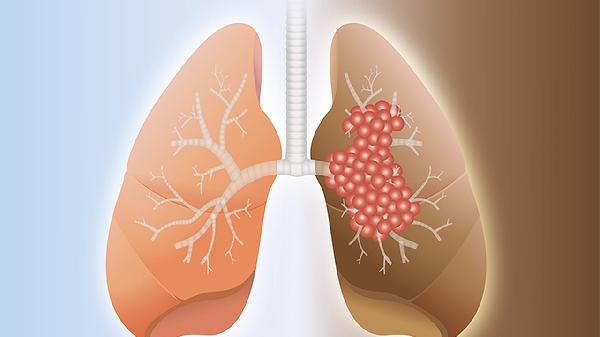

肺鳞癌晚期患者可以在医生指导下配合使用中药辅助控制病情,但无法替代手术、放疗或化疗等规范治疗。中药辅助治疗可能有助于缓解症状、改善生活质量,但具体效果因人而异。

部分中药成分可能通过调节免疫功能、抑制肿瘤血管生成或减轻放化疗副作用等方式发挥作用。临床常用的辅助中药包括黄芪注射液、康莱特注射液、华蟾素胶囊等,这些药物需在肿瘤科医生指导下使用。中药治疗肺鳞癌的临床研究数据有限,目前尚无明确证据表明单用中药可控制晚期肿瘤进展。部分患者使用中药后可能出现食欲改善、疼痛减轻等主观症状缓解,但需警惕虚假宣传或过度依赖中药延误规范治疗。

个别案例报告显示,某些中药复方可能延缓肿瘤生长速度,但缺乏大样本随机对照试验验证。传统中药方剂如肺积方、清肺解毒汤等需严格辨证施治,自行服用可能引发肝肾损伤等风险。部分中药成分可能与靶向药物产生相互作用,影响治疗效果或增加毒性反应。